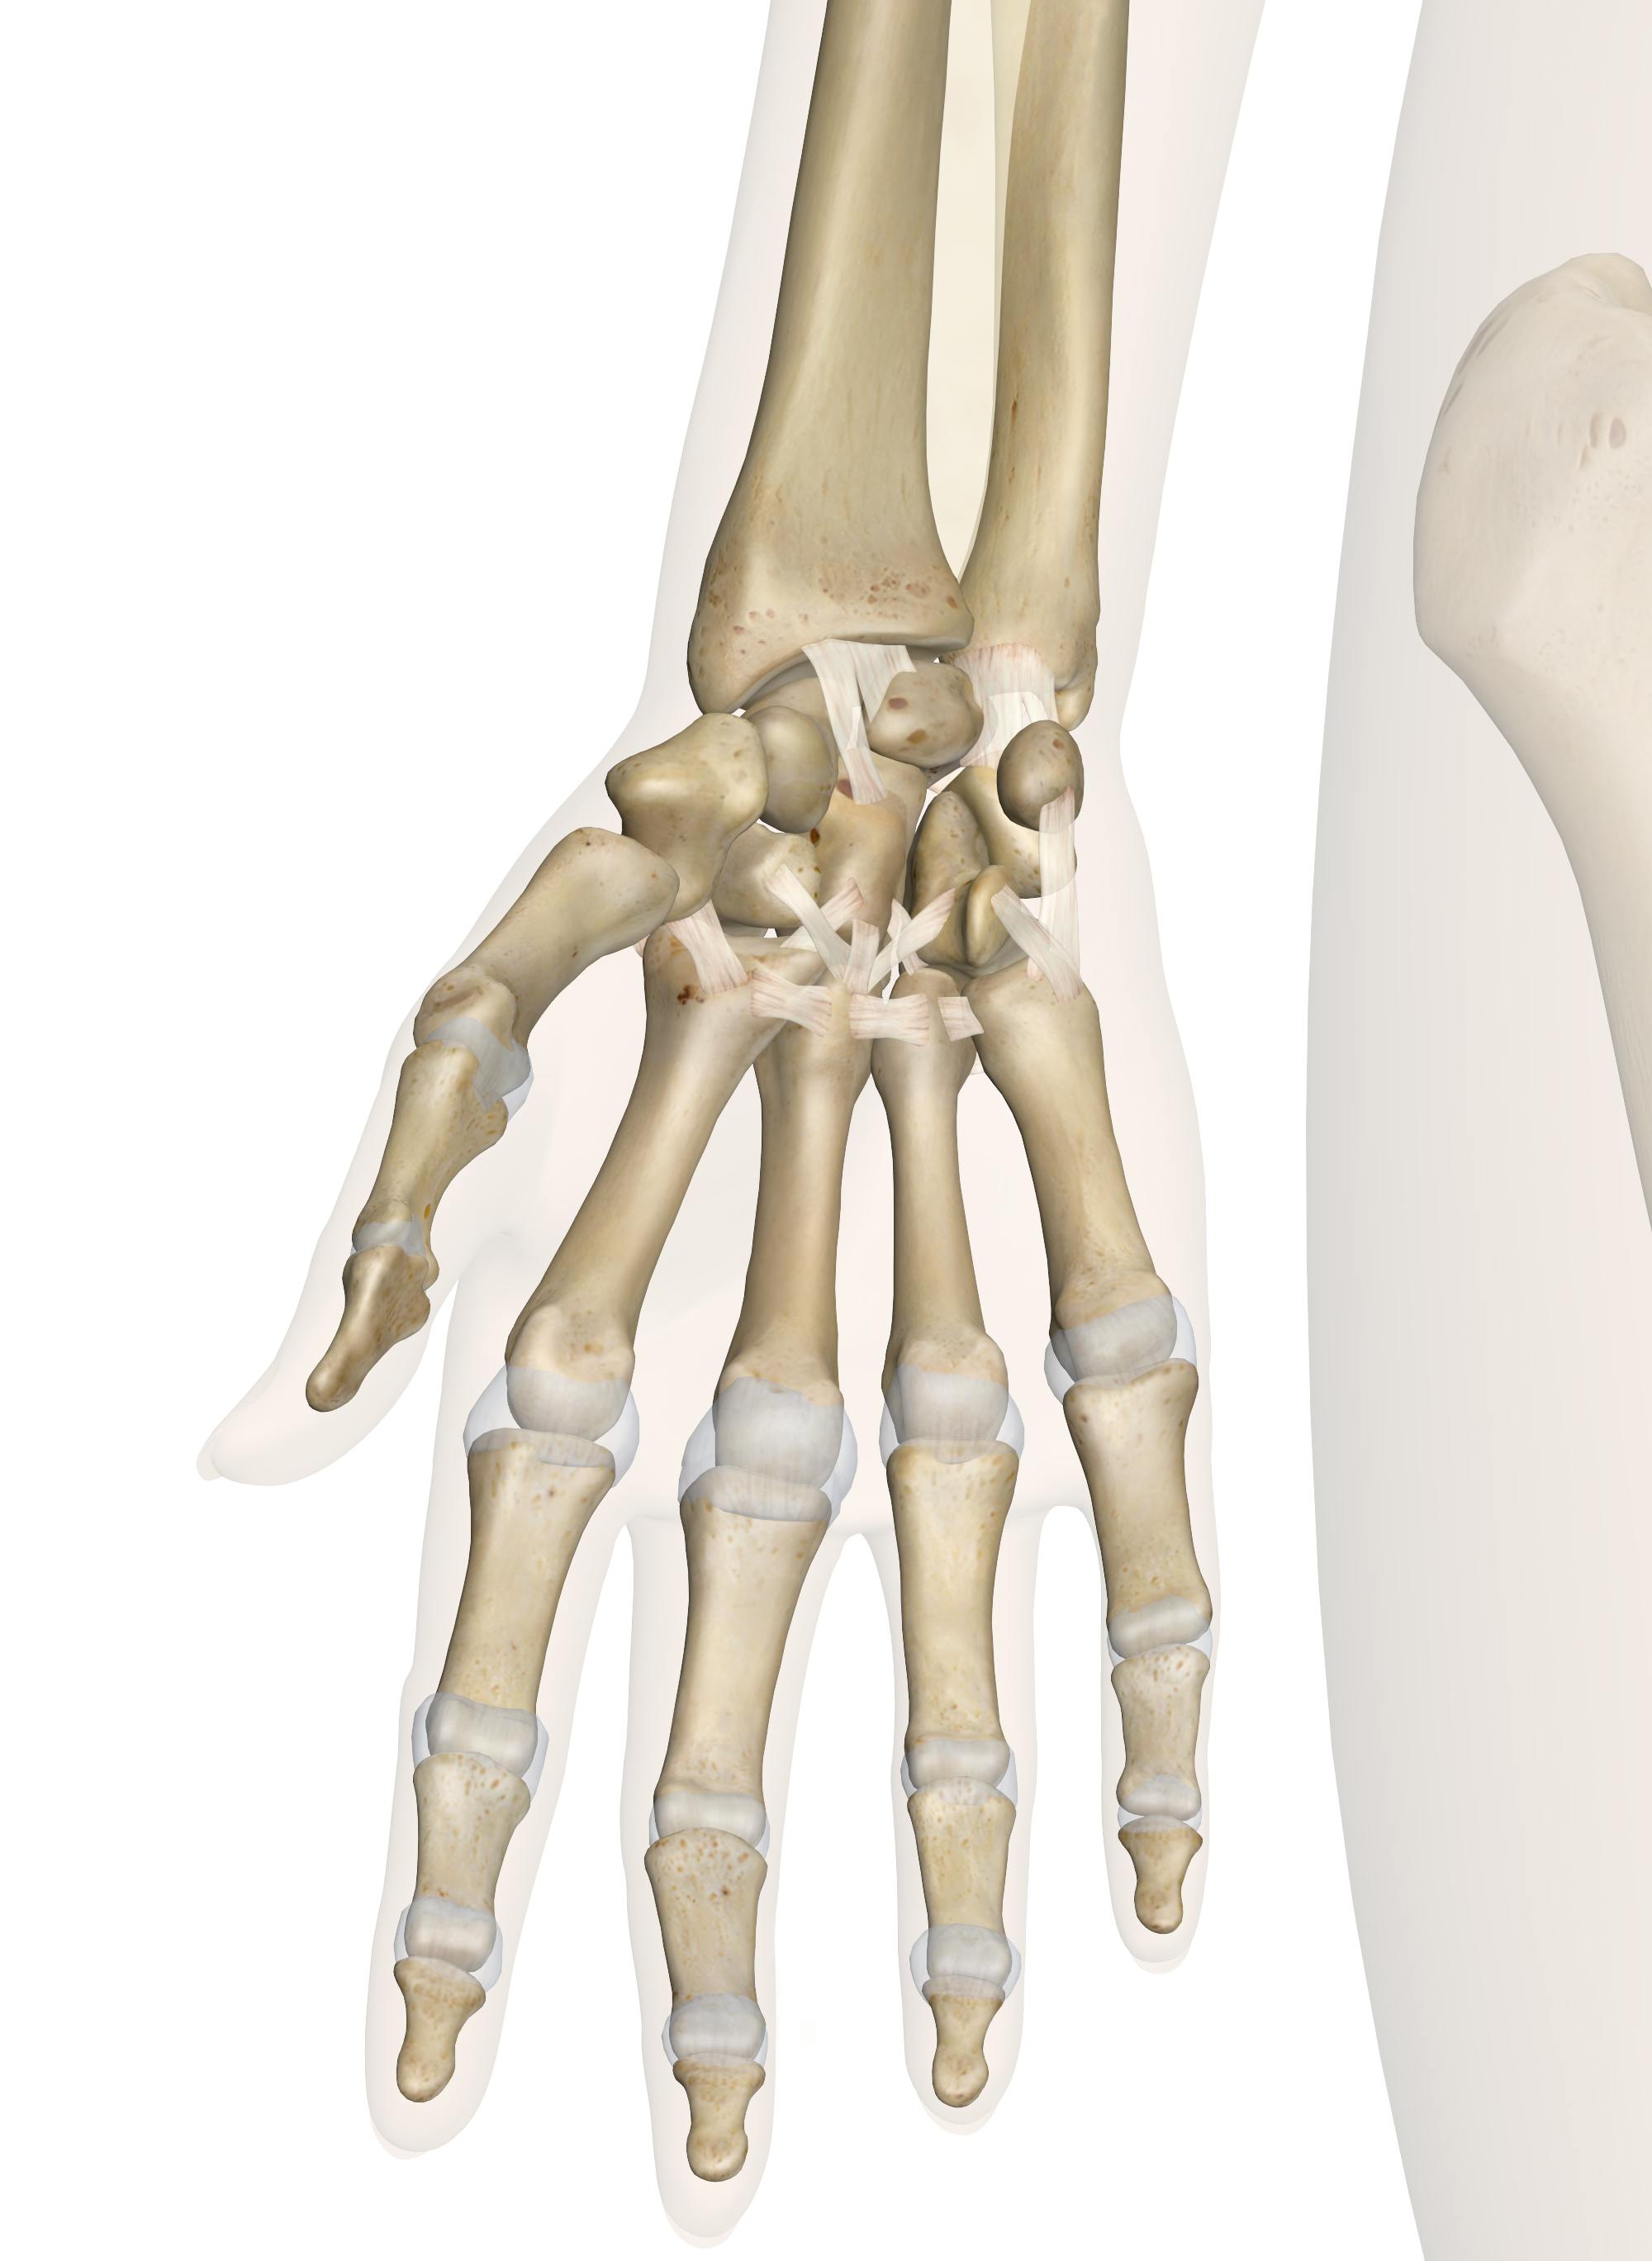

Анатомия кисти руки и строение костей